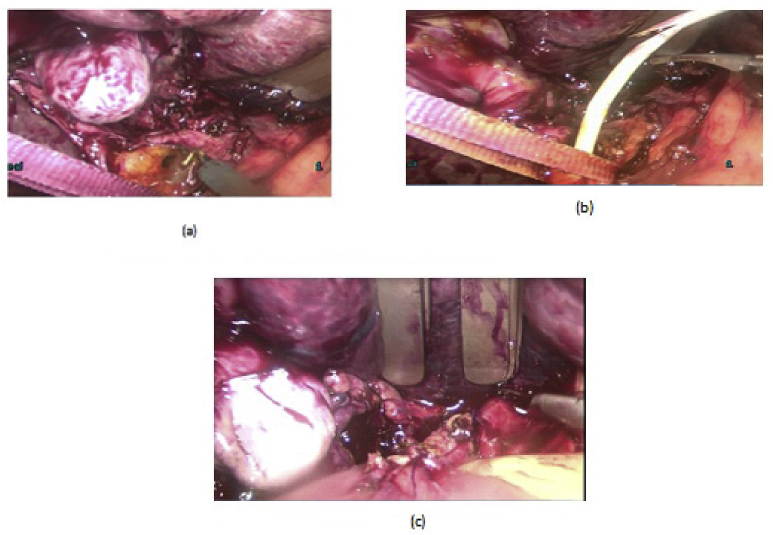

LCD: Under general anesthesia; we used the standard four-port technique of LC. Routine trans-cystic intra-operative cholangiography (IOC) was performed in all cases for identification of stones number, site and size. The gallbladder was left in situ for retraction until the operation was completed. When we reached CBD, a longitudinal supraduodenal choledochotomy(1.5–2 cm) was done using scissors or cautery. The CBD stones were entirely retrieved in all patients using cholecodoscopic extraction techniques (4.5-Fr flexible choledochoscope; Karl Storz, Tuttlingen, Germany) by irrigation, balloon or basket with mechanical lithotripsy when needed. The epigastric port was used to accommodate the operating choledochoscope [ref. 15,ref. 18,ref. [26], ref. [27], ref. [28], ref. [29]]. After all stones were retrieved and clearance of the bile duct was confirmed with choledochoscopy, the choledochotomy was closed with interrupted 4.0 Vicryl sutures in patients with primary closure of CBD and then IOC was done through the cystic duct to confirm absence of stones and leak (Fig. 1). On the other hand, for patients with T-tube drainage, the T-tube was placed in the choledochotomy and secured with sutures, Patients had a cholangiogram on the 6th postoperative day. If the finding was normal, the T-tube was clamped and patients were discharged home with the T-tube in situ then it was removed from 4 to 6 weeks later after normal tube cholangiogram in the outpatient clinic. [ref. 23,ref. 27,ref. 30]. Lastly, laparoscopic HJ was done by 4.0 polydioxanone (PDS) sutures (posterior and anterior interrupted sutures) and a tube drain was placed near the anastomosis and removed days after the operation (Fig. 2) [ref. 1,ref. 14,ref. 31,ref. 32].

OCD: It started by open cholecystectomy (OC) and IOC through the cystic duct; then identification of CBD and the junction between the cystic duct and the CBD were done. A complete Kocher’s maneuver was performed in order to feel the retro- and intra-pancreatic portion of the CBD for easy extraction of stones and to feel the papilla. Then, two stay sutures were placed transversally at the right and left portions of the duct; then the anterior wall of the supraduodenal part of CBD was opened. The incision was performed with a sharp scalpel, then an exploration of the CBD first proximally and then distally with the Randall forceps occurred for extraction of visible stones. The proximal and distal CBD was then irrigated with saline using a soft catheter. In choledochoscopic cases, the CBD stones were entirely retrieved using choledochoscopic extraction techniques (4.5-Fr flexible choledochoscope; Karl Storz, Tuttlingen, Germany) (Fig. 5, Fig. 6). After all stones were extracted and clearance of the bile duct was confirmed; the management was as mentioned in LCD (Fig. 3, Fig. 4). Lastly, in HJ cases, the biliary-enteric anastomosis was done by 4.0 PDS sutures (posterior continuous and anterior interrupted sutures) [ref. 20].